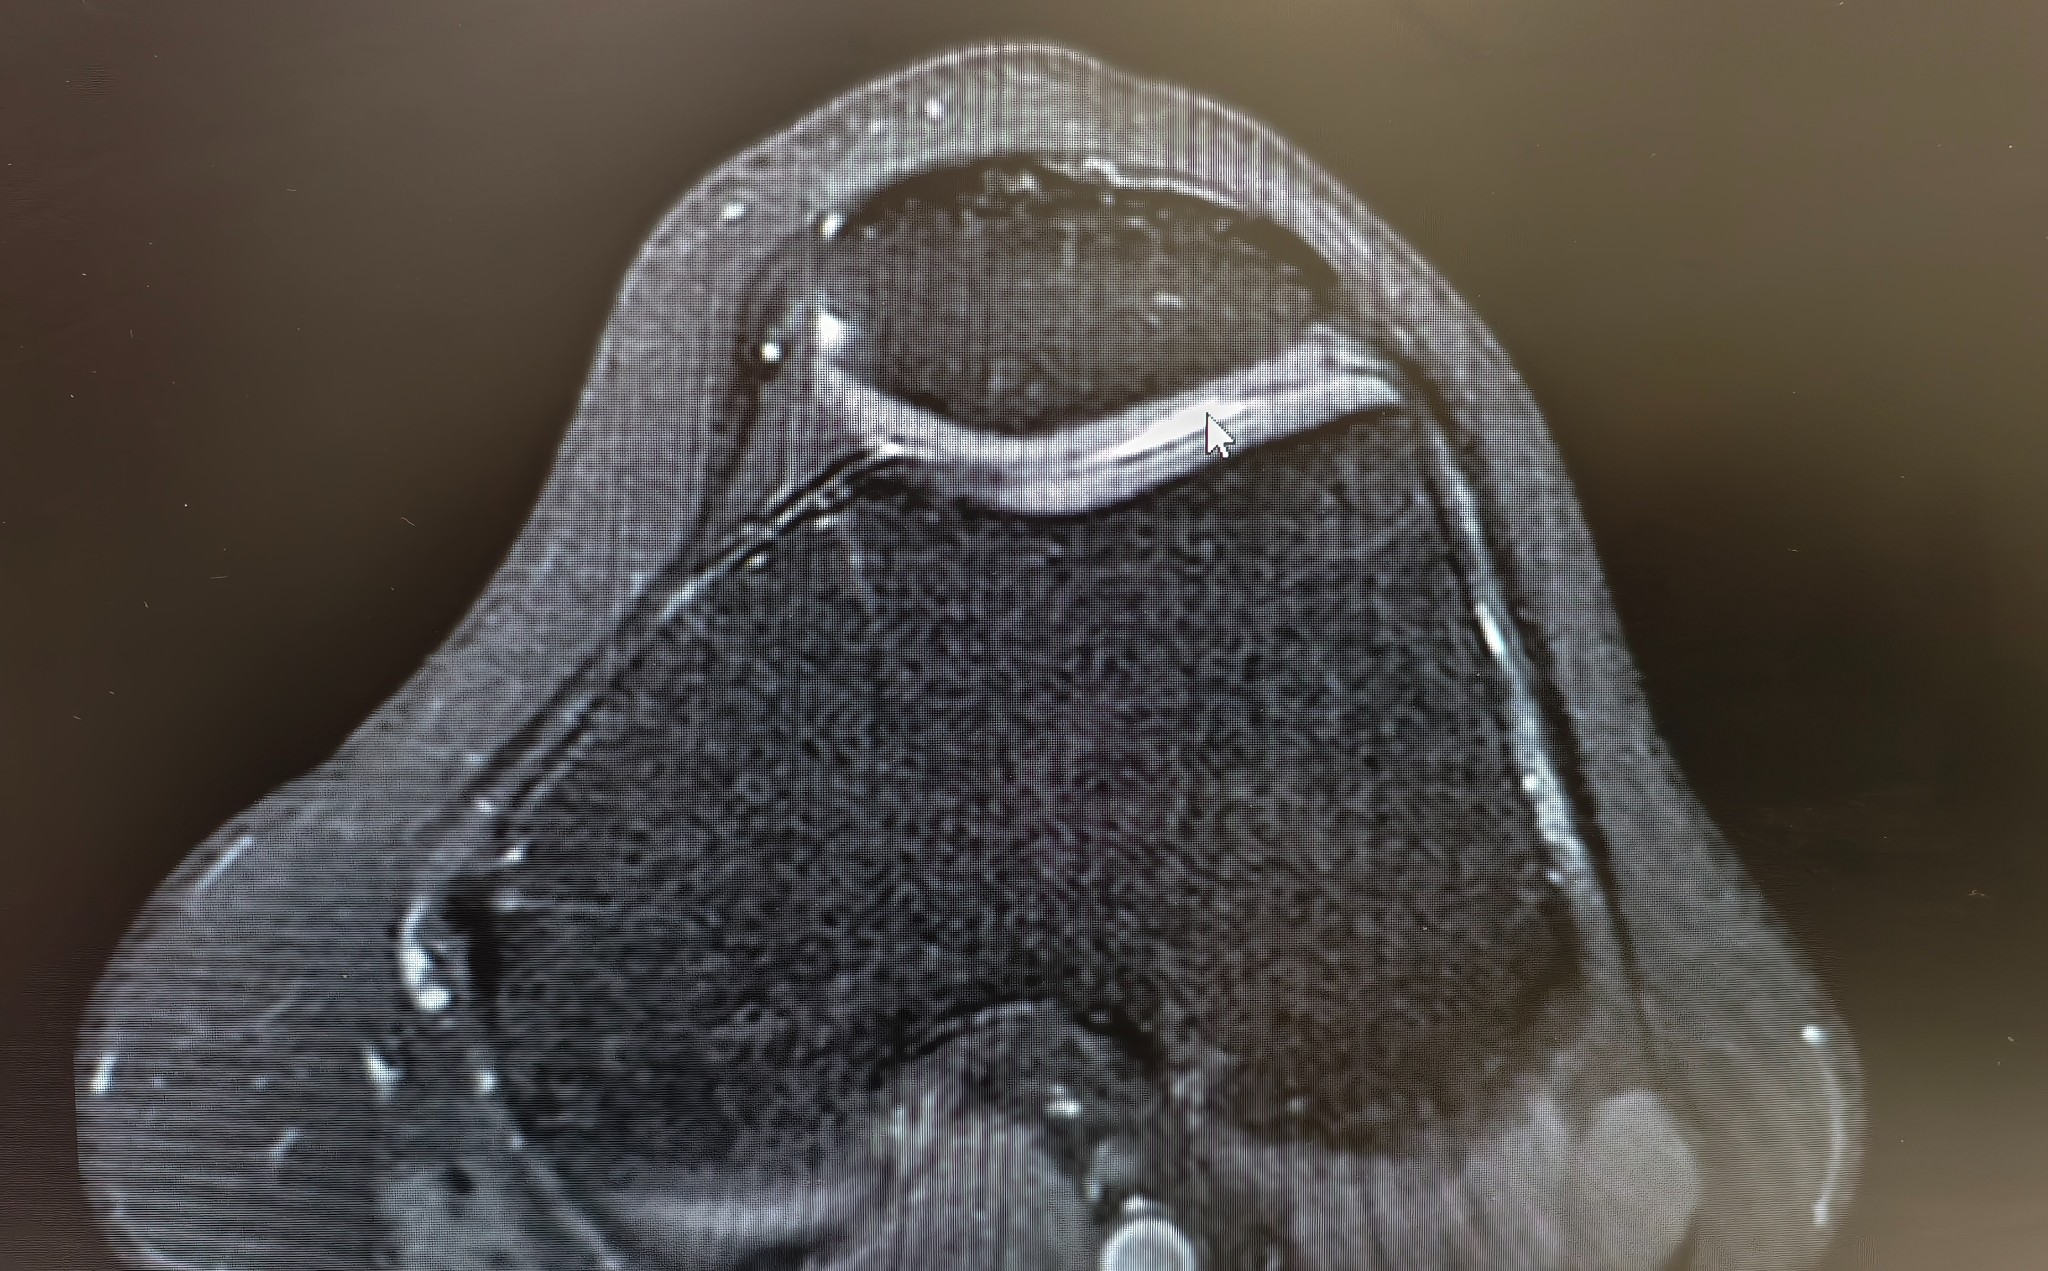

ภาพ mri ประกอบครับ

1. จากภาพประเมินได้เป็นเกรดอะไรบ้างครับ

แพทย์ 2-3 ท่านบอกว่า น่าจะอยู่ที่ระดับ 2 ค่อนไป 3